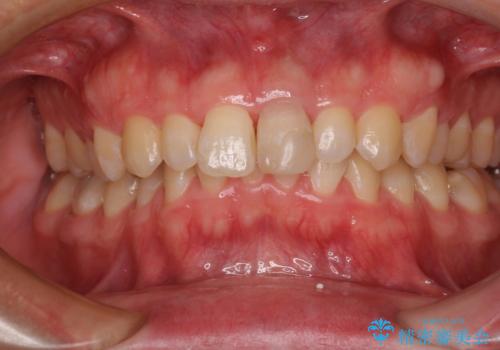

- 転んだ際に欠けてしまった前歯の変色が気になるとのことで来院された患者様です。

診察やレントゲン写真より神経組織の失活が認められたため、根管治療、ファイバーコアによる土台築製後、オールセラミッククラウンにて補綴することとしました。

神経を取り除いた歯は時間とともに変色してきます。

クリーニングやホワイトニングでは改善できないため、オールセラミッククラウンなどによる補綴治療が必要となります。